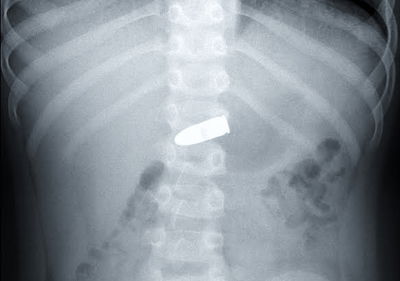

הרופאים בשניידר חשבו שכבר ראו הכל, אך צילום הרנטגן הזה הדהים אותם. בבטנו של הילד בן ה-5 נמצא קליע אקדח שבלע. חבלן משטרתי הוזעק לייעץ לרופאים. "מדובר במקרה נדיר מאד, בו גוף זר מסוכן נמצא בגופו של ילד קטן" אמר הרופא המטפל, ד"ר ערן משיח (בריאות)